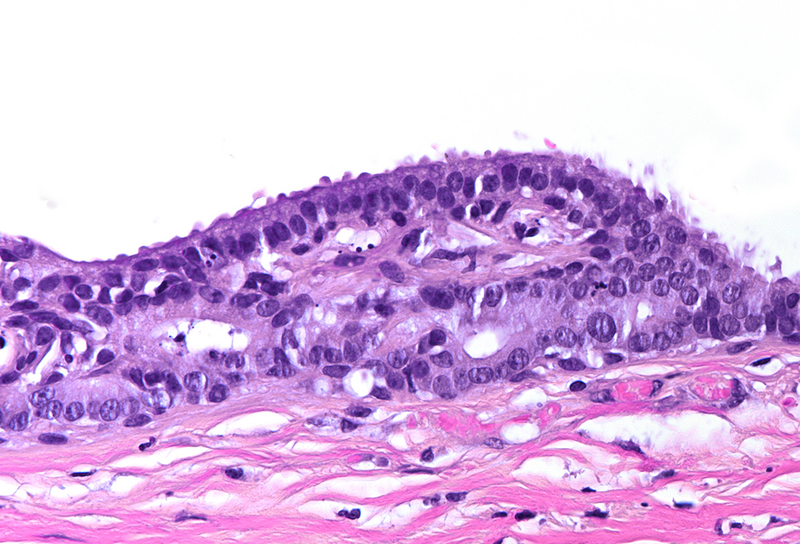

Histological examination disclosed a hybrid cyst lining epithelium, composed of a luminal layer of columnar cells with slightly basophilic cytoplasm and signs of mucin production, while slightly darker cuboidal cells without specific differentiation were present basally (Panel B-C). The cells exhibited mild nuclear irregularities, but no true dysplastic or malignant features were observed. The fibrotic cyst wall contained no skin adnexal structures, neural tissue, smooth muscle bundles or specific stroma. Immunohistochemical studies showed strong and diffuse reactivity for cytokeratin 7 of both epithelial layers (Panel D). In addition, the basal epithelial cell layer demonstrated immunoreactivity for cytokeratin 5/6 (Panel E) and p40 (Panel F). No immunohistochemical reactivity was observed for CDX2, CK20, PAX8, estrogen and progesterone receptors. Based on the morphological and immunohistochemical features, the diagnosis of a benign cyst lined by anal gland epithelium (“anal gland/duct cyst”) was made.